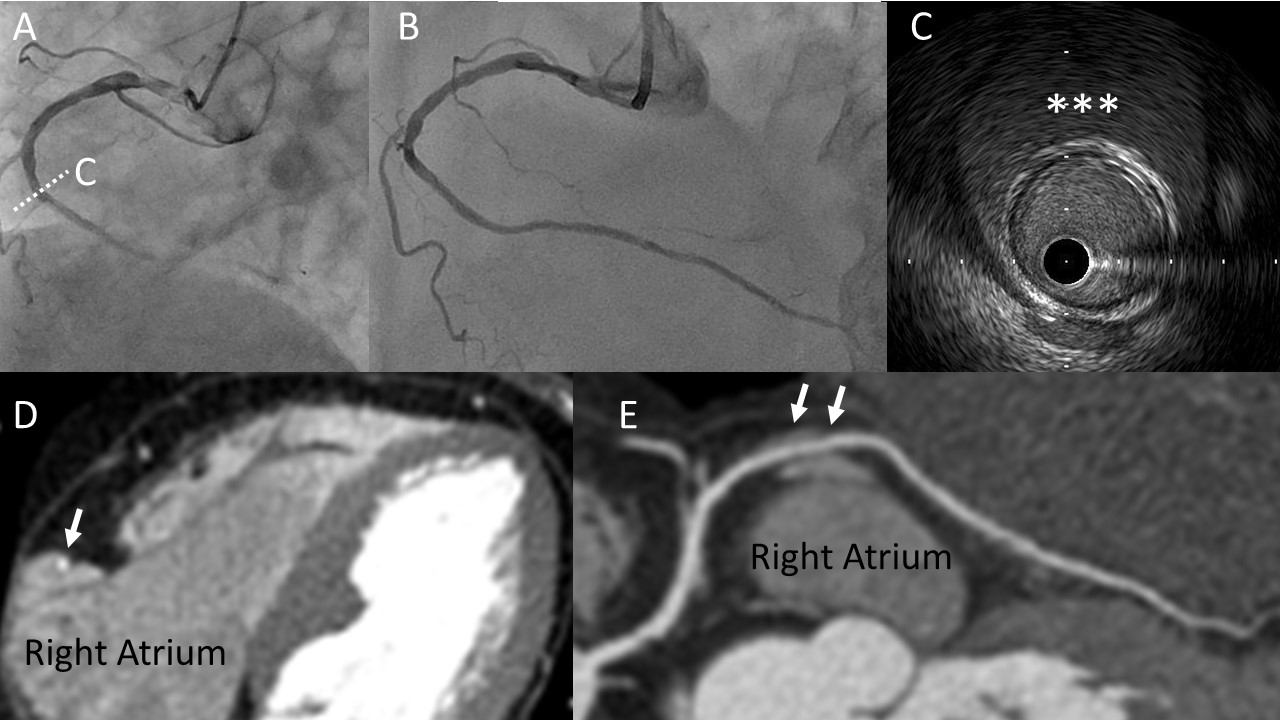

A 70-year-old woman with a history of type 2 diabetes mellitus was transferred to our hospital due to inferior ST-segment elevation myocardial infarction. An emergent coronary angiogram revealed occlusion of the distal right coronary artery (Figure 1A). Primary percutaneous coronary intervention was performed, preceded by lesion assessment using intravascular ultrasound (IVUS). The IVUS examination revealed a large encapsulated effusion surrounding the mid coronary artery, which was not connected to the coronary artery itself (Figure 1C). However, a coronary angiogram did not detect any abnormalities in this lesion (Figure 1A).

Although it was challenging to discern this texture in the emergent situation, we proceeded with intervention for the culprit lesion of the distal right coronary artery. Following the successful coronary intervention (Figure 1B), computed tomography confirmed that the mass identified was part of the right atrial appendage (Figure 1D, E). Middle of the right coronary artery ran adjacent to the right atrial appendage. Repeat angiogram after 1 year did not show significant stenosis in the right coronary artery. IVUS is a valuable tool for the assessment of intra-coronary artery structures and its findings can contribute to safe and effective interventions. While most interventional cardiologists may not typically focus on structures outside the coronary artery, IVUS can also provide insights into these external structures. Furthermore, high-resolution IVUS can aid in evaluating structures outside the coronary artery.